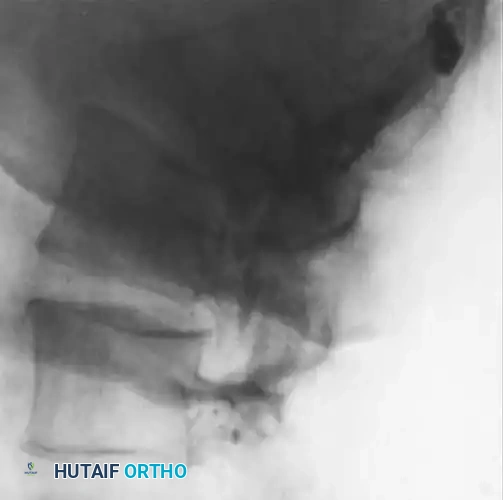

Fig. 40-7A: Early radiographic appearance of spinal osteomyelitis demonstrating minimal disc space narrowing, but a relatively normal endplate and subchondral region.

As the infection progresses (typically 2 to 8 weeks), the destructive cascade becomes evident. Findings include profound disc space narrowing, endplate destruction, defects in the subchondral bone, and reactive hypertrophic (sclerotic) bone formation.

Fig. 40-7B: Progressive infection showing a severe reduction of disc height associated with the destruction of the endplate and the development of subchondral lytic defects.